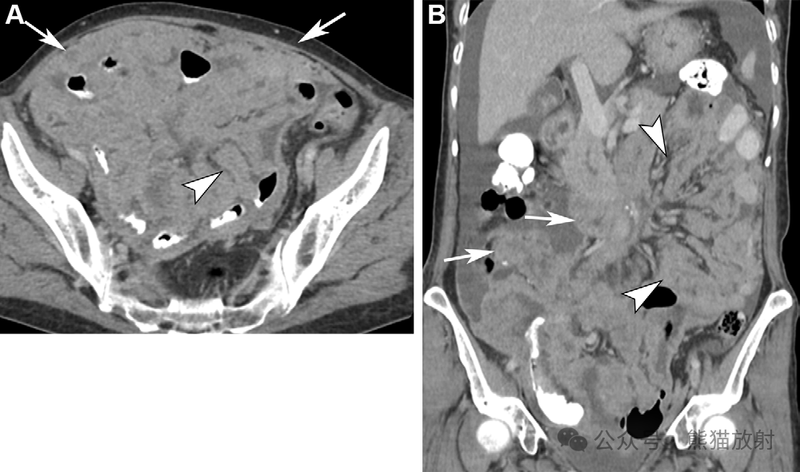

不同类型腹膜间皮瘤两例。(A,B) 46岁男性,湿型上皮样腹膜间皮瘤。腹盆部轴位(A)和冠状 (B) 对比增强 CT 图像显示腹膜不规则增厚,网膜饼形成 (箭)和严重腹水(箭头)。(C,D) 56岁女性,干型上皮样腹膜间皮瘤。腹部轴位增强 CT (C) 和T2WI (D) 图像显示大网膜明显饼状增厚 (箭)。

66岁男性,腹膜间皮瘤,主要累及小肠系膜。腹盆部的轴位 (A) 和冠状 (B) 对比增强 CT 图像显示腹膜结节状增厚(箭)伴小肠系膜片状软组织增厚(箭头),肠系膜呈星芒状表现。